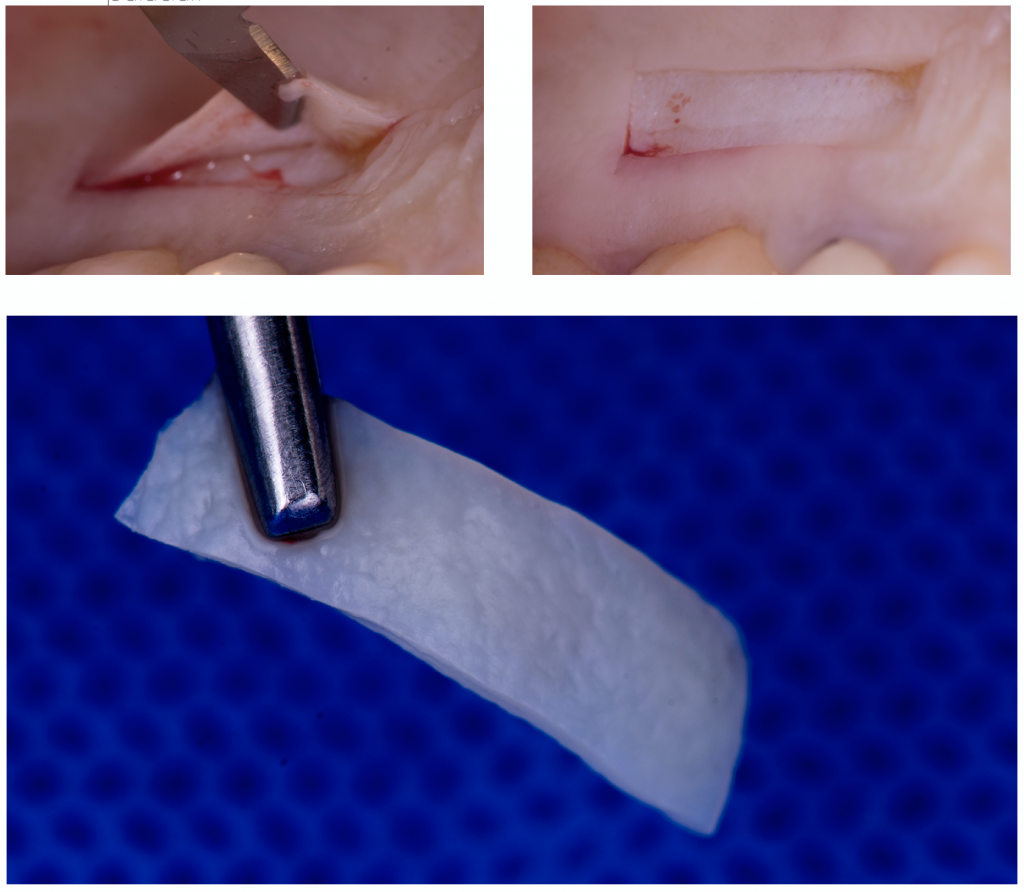

Paso a paso de Colgajo Desplazado Coronal + Injerto de Tejido Conjuntivo

6. Utiliza injerto gingival libre des-epitelializado (IGL - D)

La toma del injerto es uno de los momentos de mayor tensión para un estudiante, debido a las complicaciones que se pueden presentar. Tienes dos técnicas para tomar el injerto: IGL-D e incisión lineal. La incisión líneal permite una cierre por primera intención, resultando en ventajas favorables para la cicatrización y dolor post - operatorio. Sin embargo un IGL- D presenta muchas ventajas:

- Menor tiempo quirúrgico, comparado con tomar el injerto en incisión lineal.

- Menor riesgo vascular, las arterias se encuentran en planos más profundos y con un IGL- D trabajas más cerca a la superficie.

- Mejor calidad de tejido conjuntivo, ya que las fibras están mejor organizadas inmediatamente después del epitelio, a diferencia de planos más profundos donde encontrarás mayor tejido adiposo/ glandular.

- Visión directa, súper importante para tu primera toma de injerto del paladar.